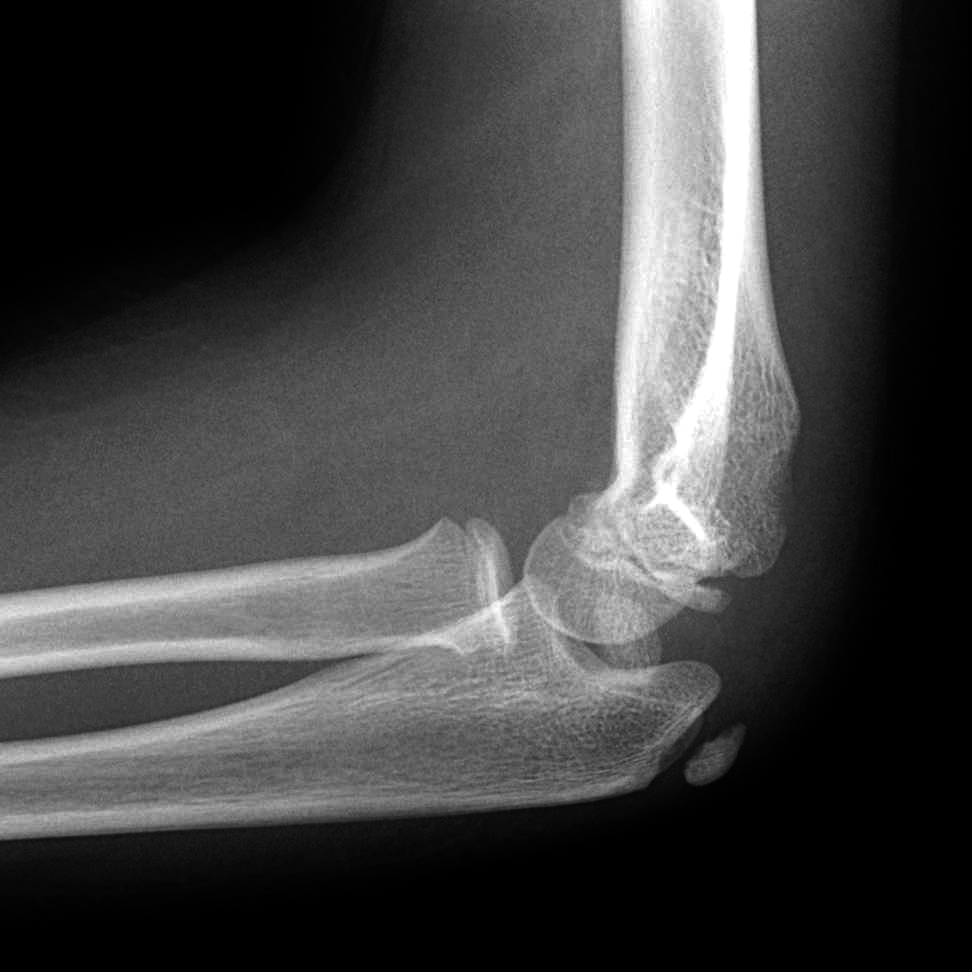

Welche wichtige, jedoch leicht zu übersehende Verletzung erkennen Sie auf diesem Ellenbogenröntgen eines 12-jährigen Patienten nach erfolgter Reposition einer vorangegangenen Ellenbogenluxation?